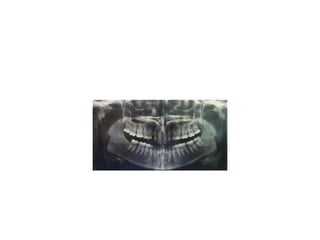

pre-op

Management of missing upp incisor

• Upper central incisors are rarely congenitally

absent. They can be lost as a result of trauma,

or occasionally their extraction may be

indicated because of dilaceration. Upper

lateral incisors are congenitally absent in

approximately 2 per cent of a Caucasian

population, but can also be lost following

trauma. Both can occur unilaterally, bilaterally,

or together. Whatever the reason for their

absence. there are two treatment options: